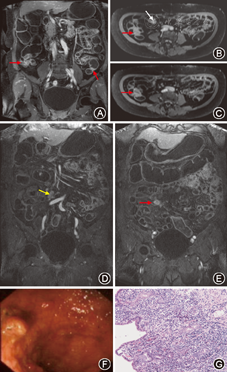

53例患者均完成MRE检查,其中诊断小肠克罗恩病12例(图1)、小肠息肉3例、小肠间质瘤3例(图2)、小肠憩室炎2例、慢性阑尾炎2例,溃疡性结肠炎3例,结肠癌1例,始基子宫1例,无器质性肠道疾病14例。12例小肠克罗恩病,MRE显示6例病变累及回盲部或末段回肠,6例表现为多节段小肠受累,受累部位肠病厚度>4 mm,强化信号比值>1.3,诊断灵敏度和特异度均为100%。缺血性肠病、小肠血管发育畸形和NASID表现为肠管的局部或阶段性管壁增厚和(或)明显强化,定位诊断正确,定性诊断为良性病灶,考虑局部肠壁炎症;2例小肠息肉于MRE未能显示(假阴性)。2例无器质性肠病患者局部肠管充盈不良,MRE考虑为局部炎症(假阳性)。ROC曲线显示MRE发现小肠病灶的曲线下面积0.900(95%CI 0.750~1.000)(P<0.01); MRE诊断小肠病灶的曲线下面积0.729(95%CI 0.573~0.884)(P<0.01); MRE和胶囊内镜两种方法在发现小肠病灶具有相关性(χ2=28.800,P=0.000),kappa值=0.800,这提示两种方法在发现小肠疾病中具有很好一致性。MRE和胶囊内镜两种方法诊断小肠疾病具有相关性(χ2=12.600,P=0.000),kappa值=0.462,这提示两种方法在诊断小肠疾病具有中度一致性。

MRE的一个重要诊断价值就是诊断克罗恩病[7]。本组研究中,以肠壁增厚>4 mm,强化信号比值>1.3为诊断标准。发现的12例克罗恩患者中,6例病变累及回盲部或末段回肠,为克罗恩病的典型患病部位;6例表现为多节段小肠受累,符合克罗恩病多发的特点;此外MRE发现2例克罗恩患者合并肠系膜淋巴结增大[8],显示MRE能够观察到克罗恩病肠外改变。研究表明[9],>15 mm的结节样病变MRE都可以检出,而<5~10 mm的病变检出率相对较低,对于<5 mm的病变是无法检出的。本研究中MRE对于肿瘤及息肉结节样病变的检出显示了较高的敏感性,通常需要在增强序列中观察。本组共8例结节样病变,其中3例为间质瘤,术前获得正确诊断;3例为多发息肉。多发息肉病变均在增强序列明确发现,而在平扫序列未能全部显示,病灶介于0.5~1.0 cm,多发。此外2例小肠息肉直径<1 cm,胶囊内镜检测到,MRE未见明显强化。